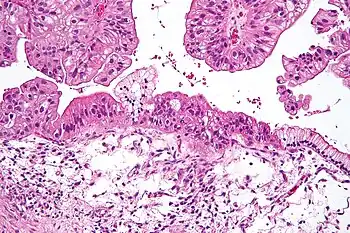

Pathology sample of a mucinous tumor of the ovary.

Benign mucinous tumors are typically multilocular (have several lobes), and the cysts have a smooth lining of epithelium that resembles endocervical epithelial cells with small numbers of gastrointestinal-type epithelial cells. Borderline and malignant mucinous tumors often have papillae and solid areas. There may also be hemorrhage and necrosis.

Cystadenocarcinomas (malignant tumors) contain a more solid growth pattern with the hallmarks of malignancy: cellular atypia and stratification, loss of the normal architecture of the tissue, and necrosis. The appearance can look similar to colonic cancer.